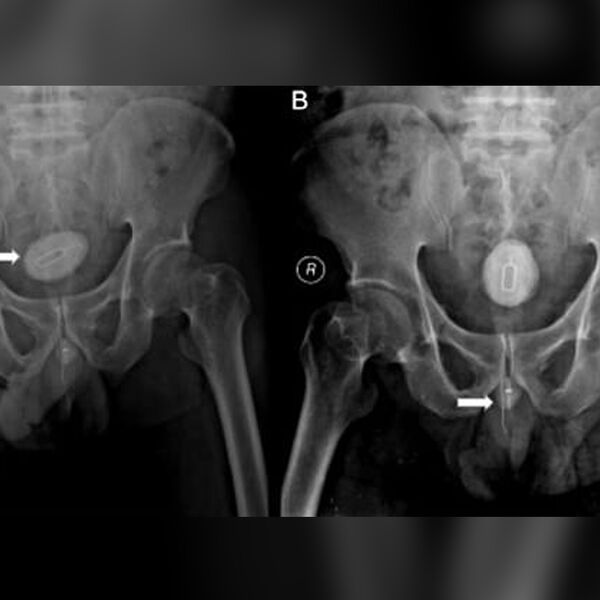

У мужчины из Индонезии удалили из уретры инструмент для извлечения SIM-карты, электрический кабель и канцелярскую резинку. Об этом сообщает Daily Mail.

48-летний мужчина из Индонезии обратился к врачам из-за боли и нарушения мочеиспускания. Пациент шесть месяцев прожил с инородными предметами в уретре. Анализы крови и мочи показали, что у мужчины была почечная недостаточность и инфекция мочевыводящих путей.

Металлический инструмент для извлечения SIM-карт привел к образованию камня в мочевом пузыре и сильной боли. Его, а также электрический кабель длиной 10 см и иглу длиной 8 см, перевязанную резинкой, удалили хирурги.